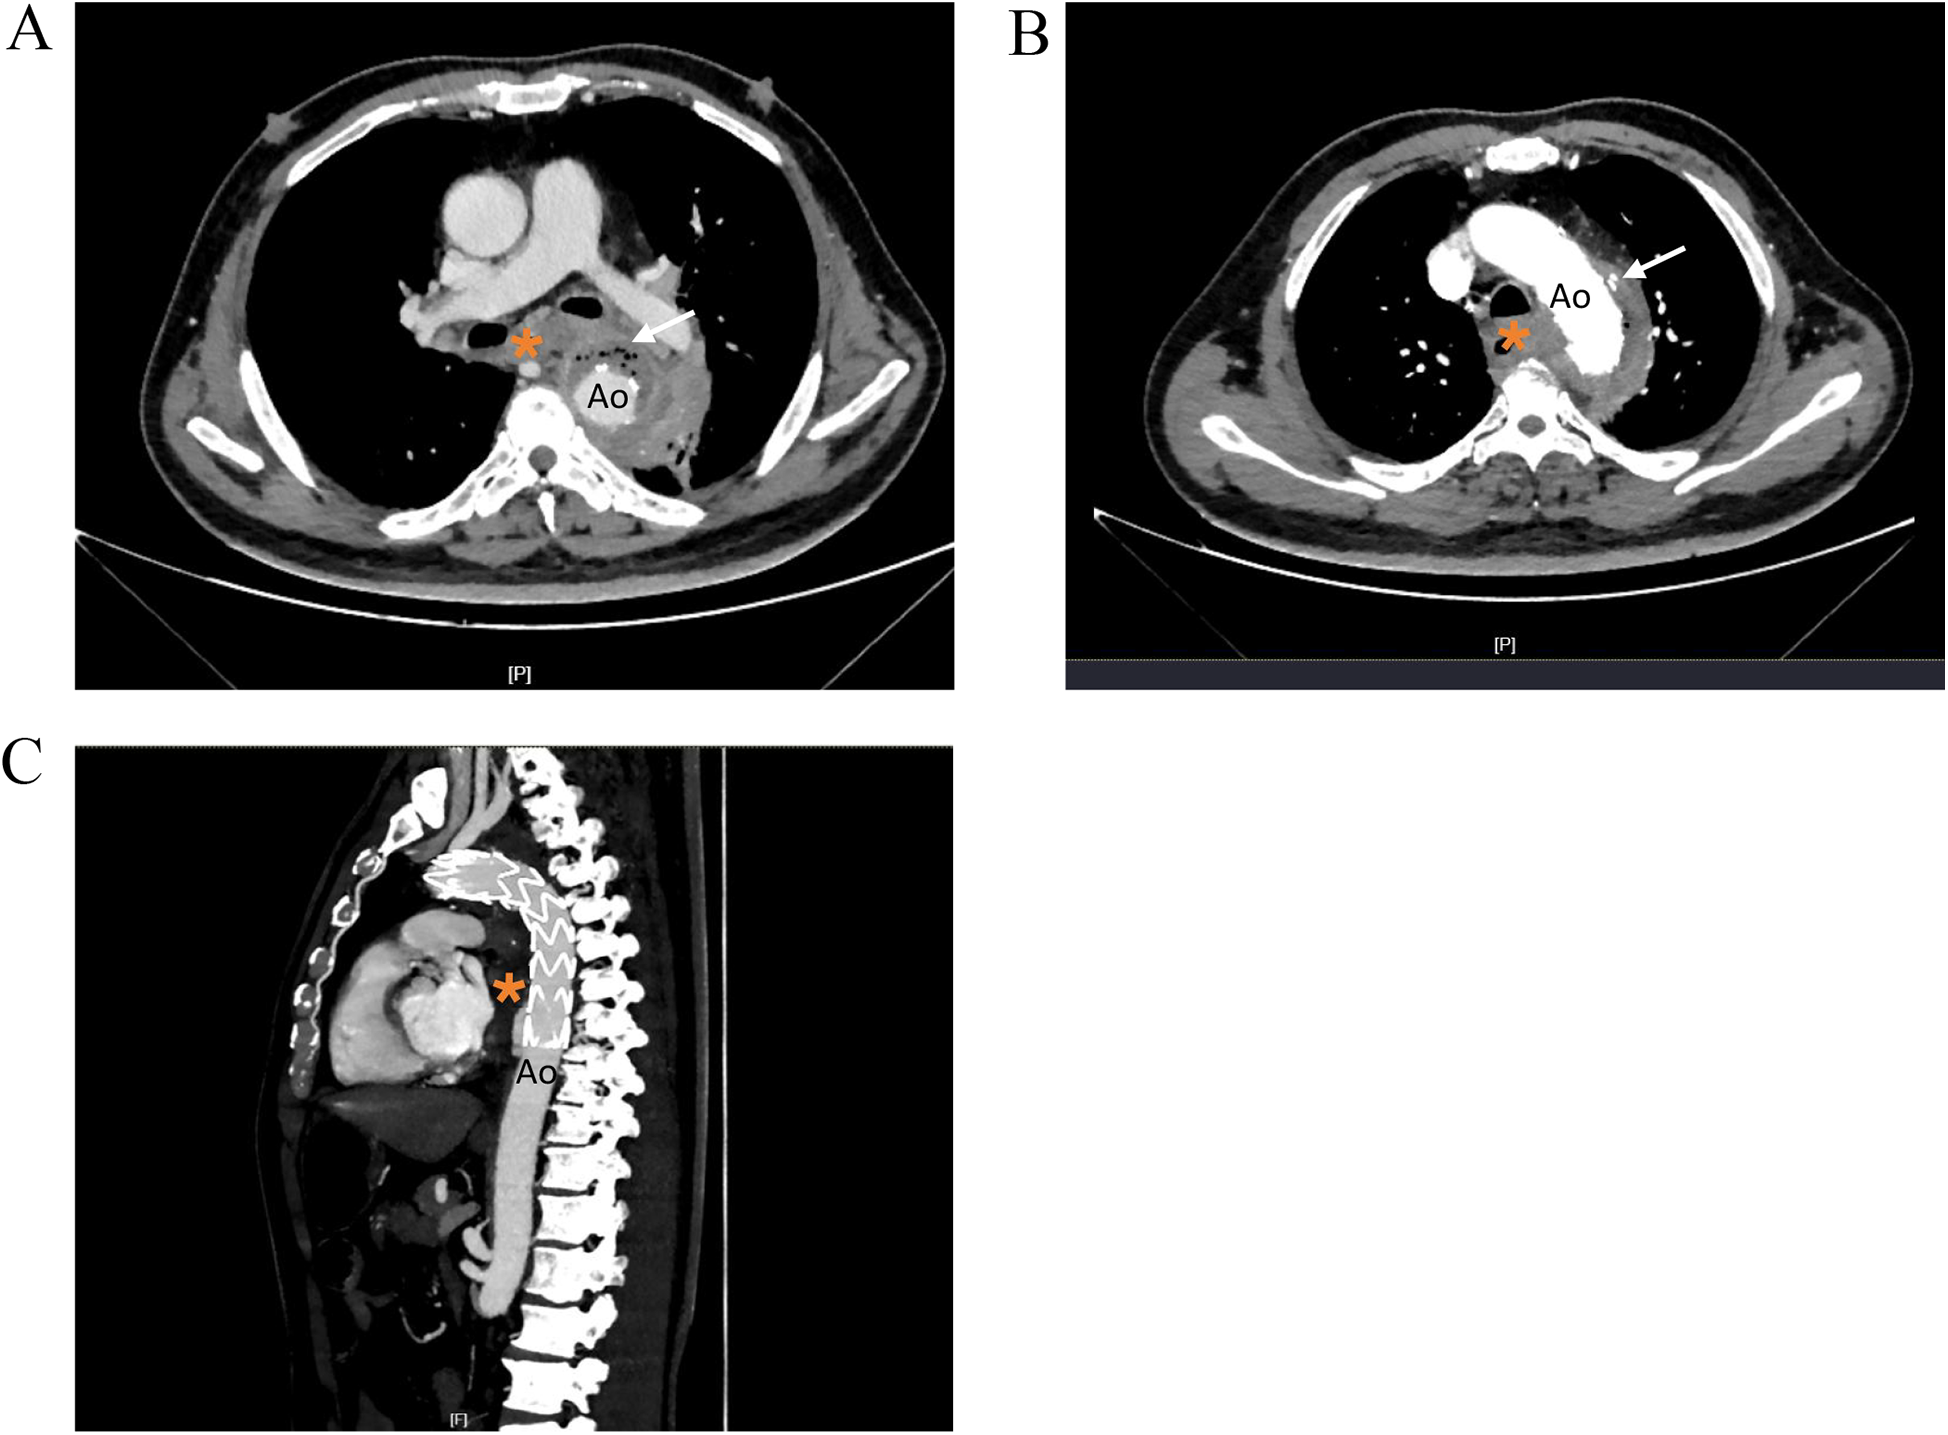

Although the patient's chest CT and echocardiogram at other hospitals showed no abnormalities, an infection related to TEVAR could not be excluded. After admission, antibiotic therapy was adjusted to meropenem [1.0, ter in die, intravenous drip (TID, iv. D)] combined with tigecycline [0.05, bis in die, intravenous drip (BID, iv. D)] for infection control. Eight hours after admission, the patient experienced dizziness and passed 400 ml of bloody stools. Emergency endoscopy revealed massive gastric hemorrhage, however, the bleeding source could not be identified, and the procedure was terminated. Subsequent thoracic aortic computed tomography angiography (CTA) suggested postthoracic aortic stent grafting, with thrombosis around the stent and the formation of a local fistula. There were low-density shadows and scattered gas shadows outside the stent, suggesting possible abscess formation. The boundary between the stent and the esophagus and lung tissues was unclear, with haziness in the mediastinal fat gap and a slight accumulation of air. There was also enlargement of the mediastinal and left hilar lymph nodes (Figure 1). Considering the patient's history of stent implantation and clinical presentation, the possibility of periaortic infection combined aortoesophageal fistula, gastrointestinal bleeding, endoleak and mediastinal abscess were considered. Oral intake was prohibited, and omeprazole and octreotide were administered continuously.

Figure 1

Thoracic aortic CTA images showing. (A) Low density shadow and scattered gas shadow around the aortic stent graf. (B) Nodular contrast imaging was observed outside the stent. (C) Sagittal reformatted images. Ao, descending thoracic aorta; *, esophagus.